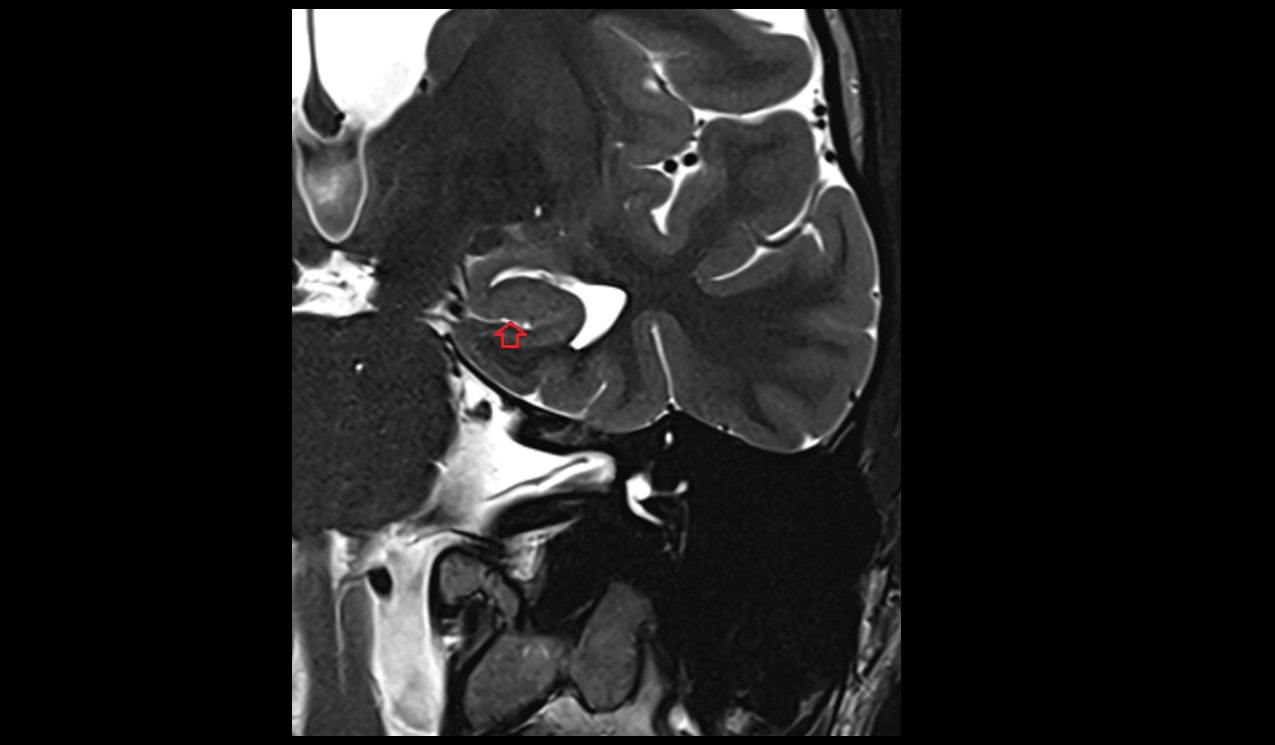

- Fetal brain

- Fetal cerebellum

- Fetal lateral ventricle